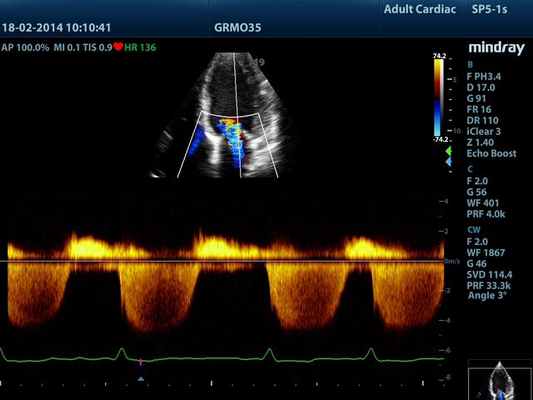

CW – режим постоянно-волнового допплера (непрерывноволновой допплер)

Постоянно-волновой допплер (continuous wave Doppler – CW) в истории допплеровской эхографии является первым используемым методом. Для использования данного режима применяются специализированные датчики: двухэлементные CW-датчики карандашного типа (pencil probe) и дуплесные датчики, которые могут работать в B-режиме.

Режим CW, в силу физических принципов работы, не имеет ограничений по скорости и глубине, но, в тоже время, он не имеет и пространственного разрешения. Режим CW имеет особую ценность при исследованиях высокоскоростных потоков в области стенозов артерий, артериовенозных шунтов, исследованиях сердца.

Рисунок 3.6. Пример исследования аортального кровотока в постоянно-волновом допплеровском режиме при аортальном пороке сердца. Исследуется кровоток вдоль всего ультразвукового луча. На допплеровском спектре регистрируется систолический поток через стенозированный аортальный клапан (AS) и диастолический поток аортальной регургитации (AI). Максимальная скорость (Vmax) стенотической струи составляет 4,1 м/с. По упрощенному уравнению Бернулли рассчитан максимальный градиент давления (Pmax) между левым желудочком и аортой, который оказался равным 67 мм рт. ст. CW Doppler Transducer — постоянно-волновой допплеровский датчик, LV — левый желудочек, LA — левое предсердие, Ao — восходящий отдел аорты, Velocity — скорость (м/с), Time — время (с). Judge K.W., Otto C.M. Doppler echocardiographic evaluation of aortic stenosis, in: Doppler Echocardiography, ed. Schiller N.B., Cardiology Clinics, 8 (2), 1990.